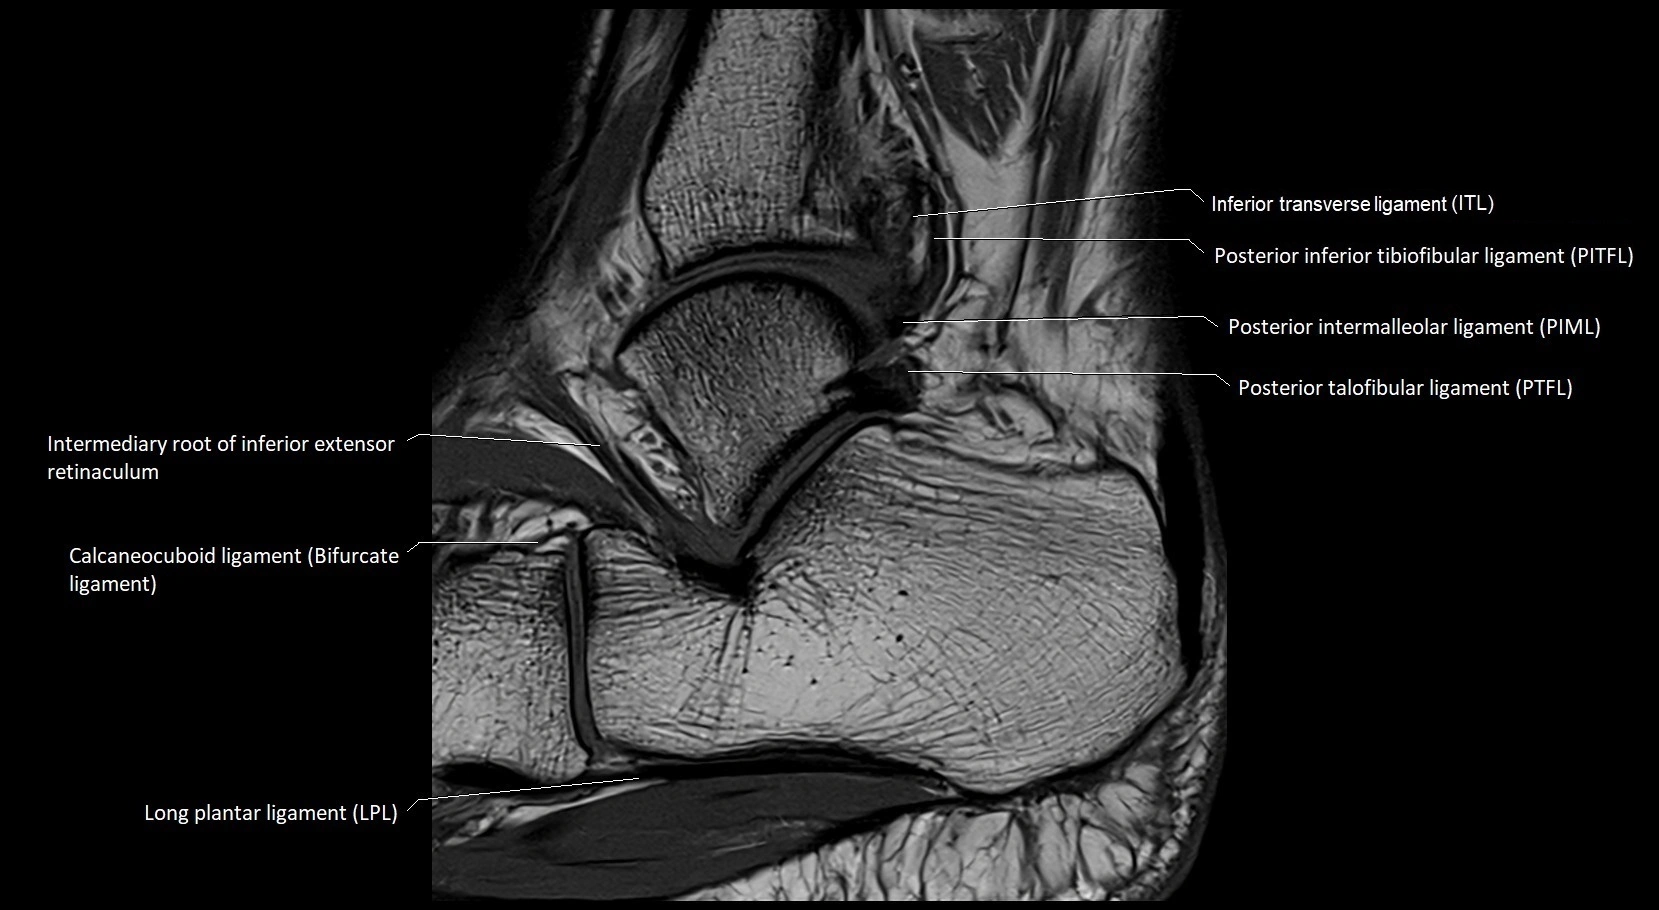

MRI image

image